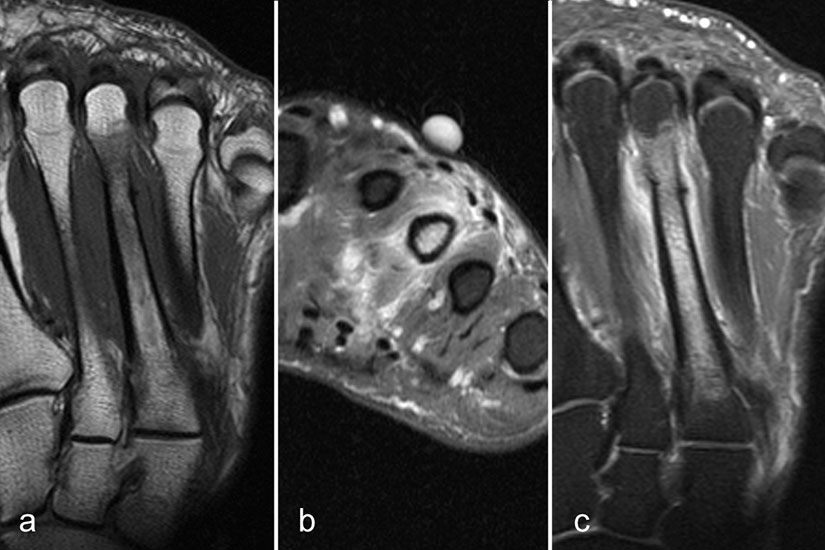

Der Begriff Morton-„Neurom“ ist im Grunde veraltet und irreführend, denn es handelt sich weder um einen Nerven- noch um einen Nervenscheidentumor, sondern um eine perineurale Fibrosierung. Da das interdigitale Gefäßnervenbündel charakteristisch in die Läsion hinein- und distal auch wieder aus der Läsion herauszieht, entsteht lediglich das Bild eines vom Nerven ausgehenden Tumors. Die charakteristischen Merkmale von Morton-„Neuromen“ sind deren Lage plantar auf Höhe der Metatarsaleköpfchen und die oft typische tropfenförmige Konfiguration (Abb. 10).

Aufgrund des hohen Bindegewebsanteils sind sie in der MRT in T2-gewichteten Bildern in der Regel auffallend signalarm, die T1 zeigt eine unspezifische Weichteilintensität. Die Anreicherung nach intravenöser Kontrastmittelgabe ist sehr variabel und erlaubt somit kaum diagnostische Rückschlüsse.

Durch seitliche Kompression des Fußes verlagern sich Morton-„Neurome“ oft weiter nach plantar in die Weichteile. Klinisch entspricht dies dem sogenannten Mulder-Zeichen 4. In der Bildgebung kann man sich den Effekt zu Nutzen machen, indem man in Bauchlage untersucht und durch die seitliche Fixierung eine entsprechende Kompression erzeugt. Die Befunde sind dann oft deutlich besser zu erkennen (Abb. 11).

Morton-„Neurome“ liegen fast immer im zweiten oder dritten Interdigitalraum. Zu beachten ist, dass Morton-„Neurome“ über lange Zeit größenkonstant sein können (Abb. 12) und kleinere Morton-„Neurome“ (unter 5 mm) sehr häufig bei asymptomatischen Gesunden beobachtet werden.